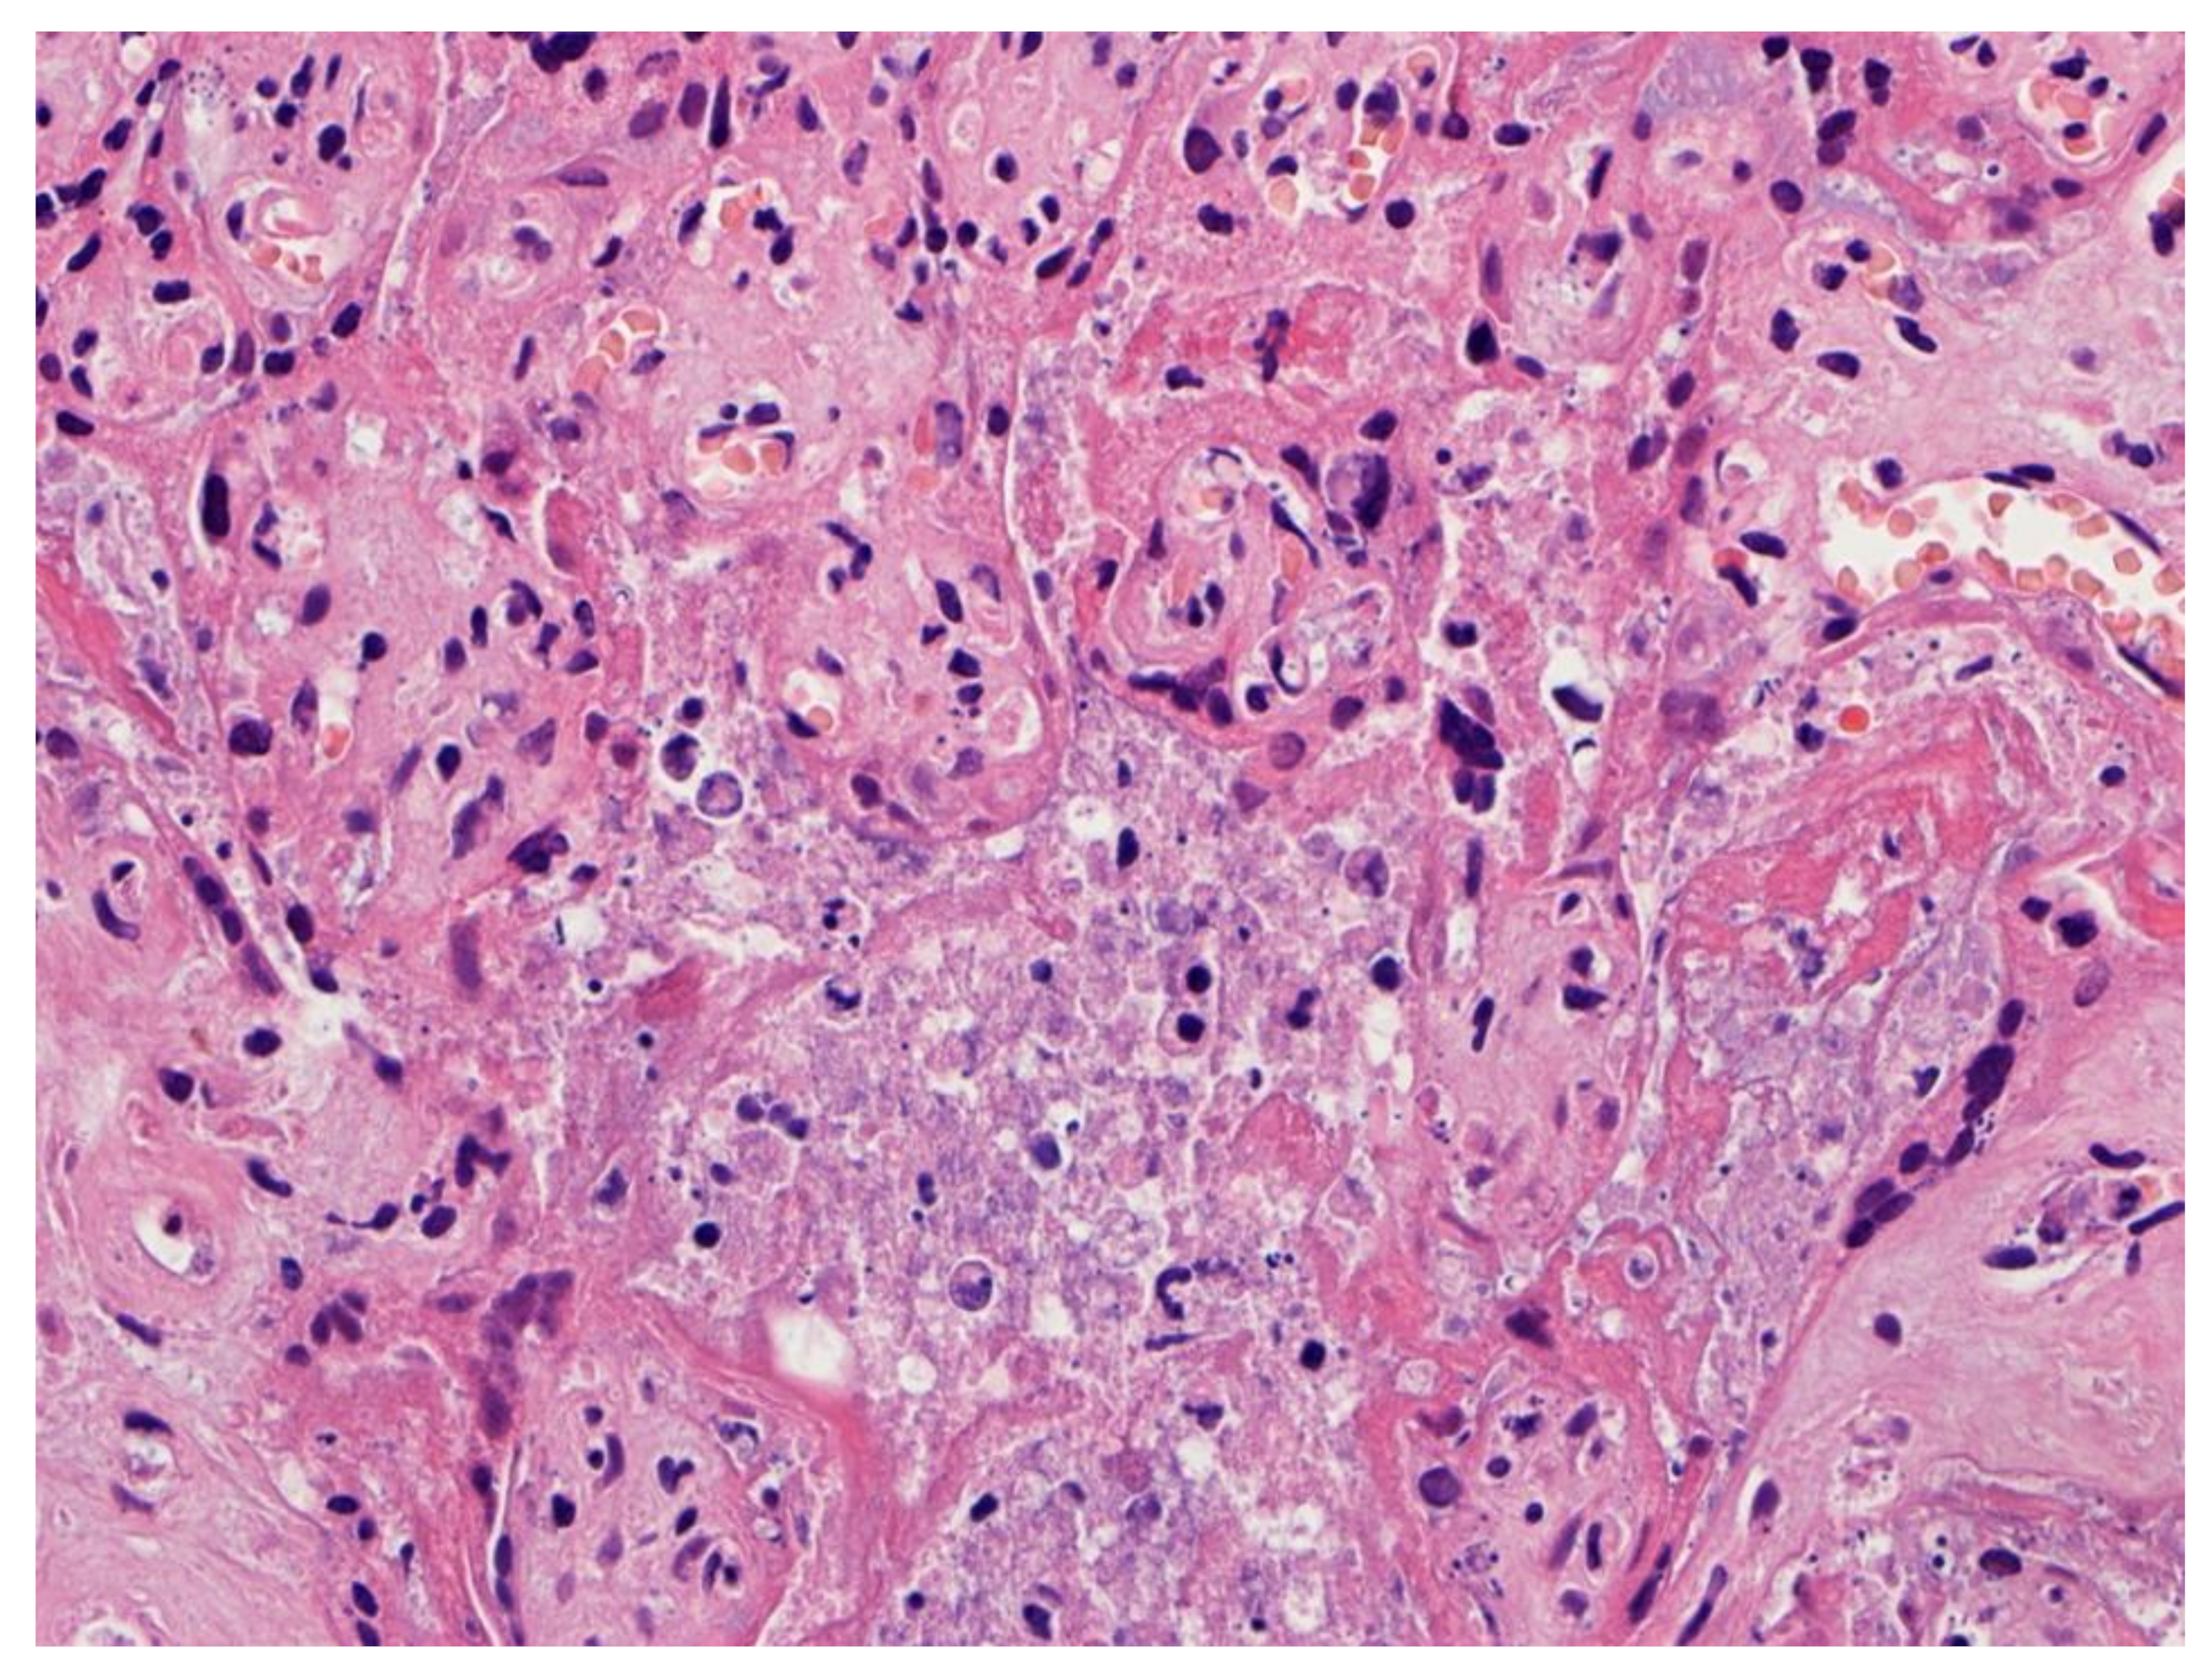

Figure 3.

Higher magnification of a placenta with SARS-CoV-2 infection and SARS-CoV-2 placentitis. There is massive perivillous fibrin deposition with ischemic necrosis of the chorionic villi and villous trophoblast. There is complete obstruction of the intervillous space with fibrin which prevents maternal blood flow though this region of the placenta. Hematoxylin & eosin staining, ×10.